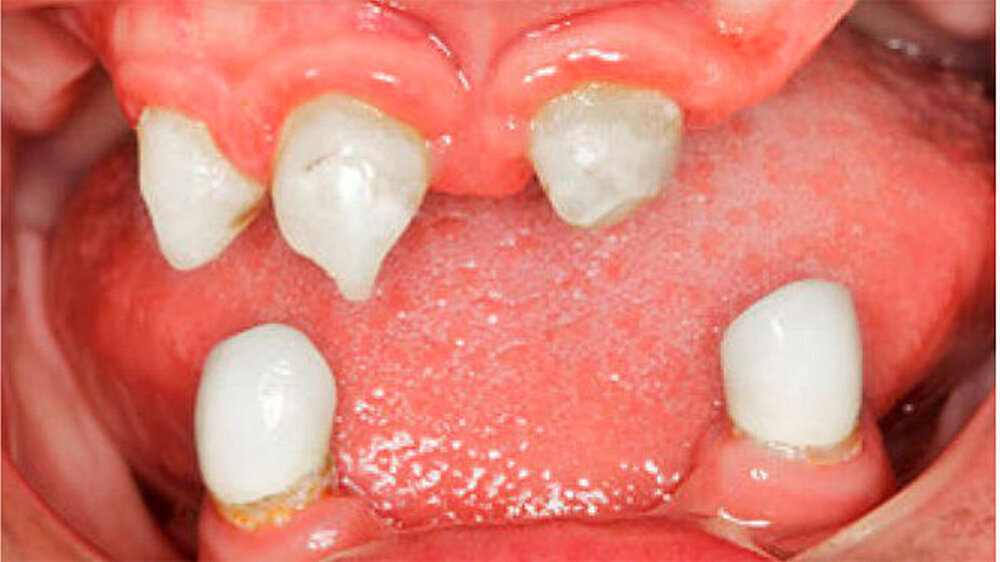

Bei dieser bei Behandlungsbeginn 16-jährigen Patientin waren seit Geburt nur die beiden ersten Molaren im Oberkiefer ausgebildet. Die Folge waren schmale und niedrige Alveolarkämme mit einem flachen Gaumengewölbe (Abb. 16 und 17). Die röntgenologische Abbildung bestätigte das geringe vertikale Knochenangebot. Eine Formanomalie der Zahnwurzeln ließ auf taurodonte Molaren schließen. Beide Molaren wiesen ausgedehnte kariöse Läsionen auf (Abb. 18).

Die Patientin war mit einer knapp neunjährigen Teilprothese im Ober- und einer zweijährigen Totalprothese im Unterkiefer versorgt. Beim Lachen wurden die nicht mehr altersentsprechenden Prothesenzähne mit den deutlichen Randverfärbungen ersichtlich (Abb. 19). Das sagittale Wachstum des zahnlosen Unterkiefers führte in den letzten zwei Jahren aufgrund der verstärkten Kontakte im Frontzahnbereich zu einer beidseitigen Nonokklusion im Seitenzahnbereich (Abb. 20). Eine rasche Verbesserung der Ästhetik als auch der Funktion war unbedingt angezeigt, um das Selbstbewusstsein dieses puberalen Mädchens zu stärken.

Aufgrund des anatomisch sehr ungünstigen Prothesenlagers war der Erhalt der Restbezahnung im Oberkiefer anzustreben. Nach Kariesexkavation und Wurzelkanalbehandlung konnten beide Zähne mit einer Wurzelstiftkappe versorgt und die alten Prothesen entsprechend umgebaut werden. Im Anschluss an die Meisterabformungen und an die Ausrichtung der Wachswälle wurden die Modelle schädelbezogen einartikuliert, und die Prothesenzähne nach ästhetischen und funktionellen Richtlinien aufgestellt. Eine bilateral balancierte Okklusionsbeziehung konnte umgesetzt werden. Im Oberkiefer wurde eine gerüstverstärkte Totalprothese hergestellt, die auf den beiden Wurzelstiftkappen 16 und 26 verankert war. Im Unterkiefer konnte die Patientin mit einer Totalprothese versorgt werden (Abb. 21 bis 23).